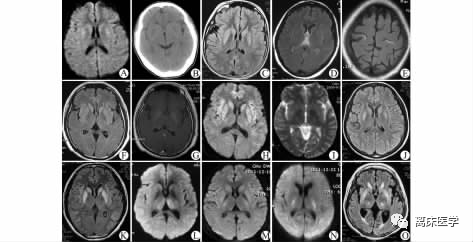

10例EPM患者的影像学表现

A和B分别为病例1的DWI 和CT图像;

C为病例2的T2 FLAIR;

D和E为病例3的T2 FLAIR ;

F~I分别为病例4的T2 FLAIR、增强扫描、 DWI 及ADC;

J、K、O分别为病例5、6、10的 T2 FLAIR;

L~N 分别为病例7~9 的 DWI。